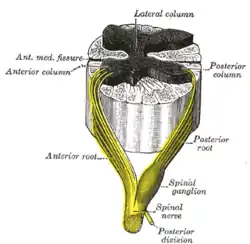

Medulla spinalis

Medulla spinalis The formation of the spinal nerve from the posterior and anterior roots